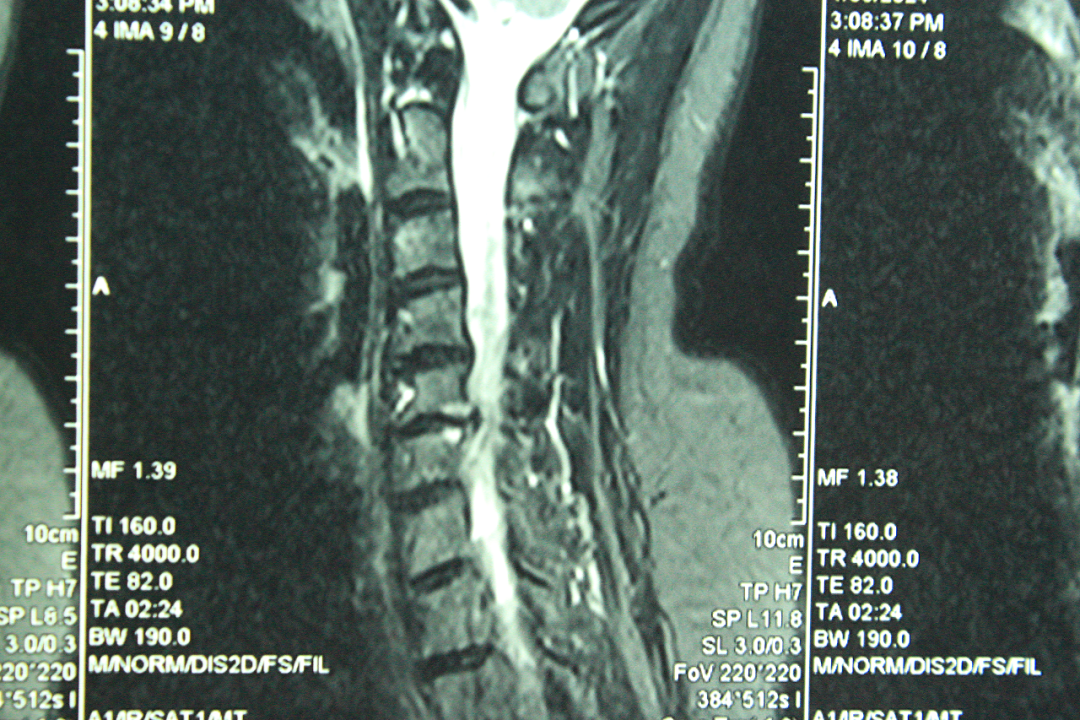

据了解,患者女性,53岁,右上肢麻木疼痛肌力减退一年加重一个月,经脊柱外科首席专家团队认真检查,CT无椎间盘钙化,MRI提示颈5/6椎间盘脱出并向下游离,初步考虑为颈5/6椎间盘突出伴神经根病,考虑选择微创手术治疗。

经过与甘肃省脊柱内镜专科联盟王想福主任会诊,病历典型,决定使用K—hole技术进行手术治疗。术后患者右上肢疼痛麻木缓解,术后第二天拔出引流管,患者情况稳定,已开始下地活动,正在积极康复中。